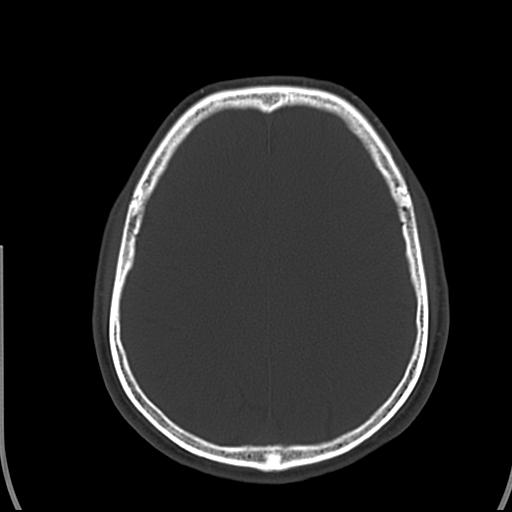

标题: CT25435:头皮下高密度影???

头皮下高密度结节影???临床上在老年男性比较常见。大家看看是什么?成因是? 本例患者,男性,51岁。外伤来诊。无染发史及发根植入史。

考虑异物。

皮下钙化点

没见过,可能为毛囊钙化。